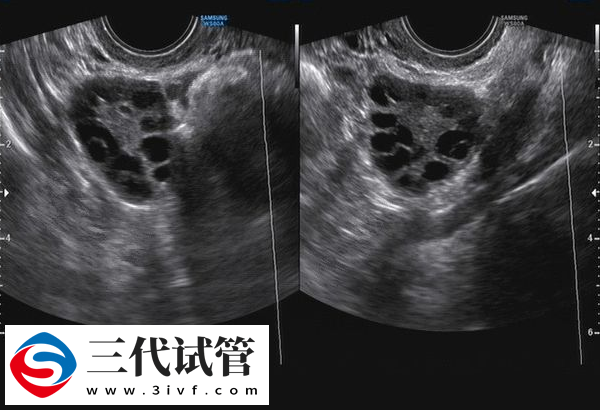

做三代试管婴儿有7个左右的基础卵泡是足够的。虽然临床上没有规定三代试管取卵数量,但是其一般最佳数量在10-15个之间,在这个范围内数量越多越好。而基础卵泡7个算是比较理想的,采用促排方案后一般都可以成功10-12个左右的卵泡,自然后期取卵数量也可以达到10个左右,经过培育筛查后移植成功率也会比较高。

做三代试管婴儿,因为需要进行胚胎筛选,一般需要取10~15个左右的卵子才行。这样获取的卵子多,通常配成的胚胎也会比较多。而7个基础卵泡数量属于比较理想的,但是如果你已经超过35岁,或者有其他生殖系统问题(如多囊卵巢综合症等),那么7枚可能就不够了。下面就为大家分析三代试管只有7个基础卵泡的成功率:

- 1. 7个基础卵泡一般经过促排后是可以获得10-12个左右的成熟卵泡,属于做三代试管较为理想的数目;